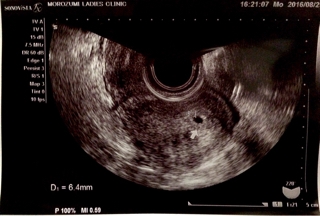

テーマ:不妊治療 昨日胎嚢が確認出来て、 ひとまず第一関門突破した感じです。 ただ、これから出産に向けて数々の関門をくぐらなければならないのかと思うと、 気が遠くなります…( ´△`;) さて、今日の様子はというと、 出血が少量、夕方から頭痛がするように。 仕事でずーっとパソコンを見続けているので、 そのせいもあるのかな。 胸のムカムカはあまりありませんでした。 あ〜早く心拍確認したいなぁ…。 ↓もし...

テーマ:不妊治療 今日は、BT17/D35(5w1d) 今まで続いていた出血は治った感じです。 ただ、たまに生理痛のような下腹部痛がします。 ◆15:23 受付(15:30受付) 思ったほど混んでいなかった感じ。 今日は両角先生がハワイで夏休みのため、 鈴木先生だけらしいので、人数調整をしているのかな? ◆15:24 看護師さんによる採血。 残りのエストラーナテープとプロゲステロン膣座薬の個数を聞かれました。 (良かった数えていて…) 採血は最初の看護師さんじゃ不安だったようで...